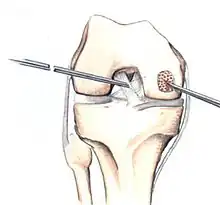

Arthroscopic image of OATS surgery on the medial femoral condyle of the knee

The choice of surgical versus non-surgical treatments for osteochondritis dissecans is controversial.[51] Consequently, the type and extent of surgery necessary varies based on patient age, severity of the lesion, and personal bias of the treating surgeon—entailing an exhaustive list of suggested treatments. A variety of surgical options exist for the treatment of persistently symptomatic, intact, partially detached, and completely detached OCD lesions. Post-surgery reparative cartilage is inferior to healthy hyaline cartilage in glycosaminoglycan concentration, histological, and immunohistochemical appearance.[52] As a result, surgery is often avoided if non-operative treatment is viable.

Intact lesions

If non-surgical measures are unsuccessful, drilling may be considered to stimulate healing of the subchondral bone. Arthroscopic drilling may be performed by using an antegrade (from the front) approach from the joint space through the articular cartilage, or by using a retrograde (from behind) approach through the bone outside of the joint to avoid penetration of the articular cartilage. This has proven successful with positive results at one-year follow-up with antegrade drilling in nine out of eleven teenagers with the juvenile form of OCD,[53] and in 18 of 20 skeletally immature people (follow-up of five years) who had failed prior conservative programs.[54]